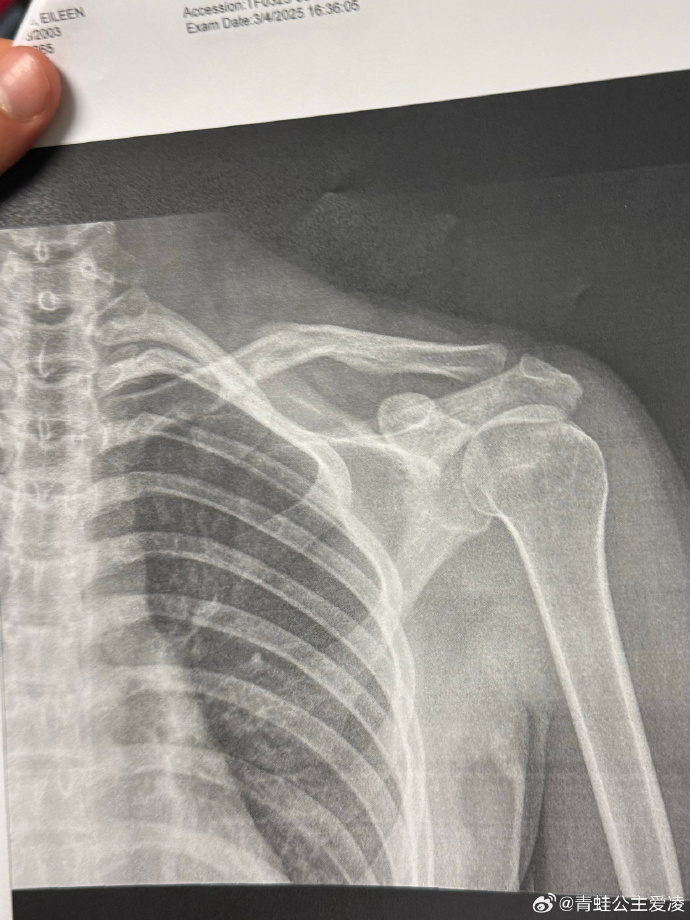

过去近一年间,谷爱凌屡受伤病困扰。今年年初在美国阿斯本极限运动会摔伤后,她遗憾缺席了哈尔滨亚冬会。3月,她在社交平台公布了锁骨骨折的X光影像。经过数月休养,她于8月重返雪场训练,不料再遇“人为事故”导致受伤。正当外界担忧其恢复进度时,她在9月通过社交媒体发布了回归雪上训练的照片,并表示经过每天长达10小时的康复理疗,已经回归雪上训练为新赛季备战。

今年3月9日,谷爱凌在社交媒体晒出肩部骨折的X光照片,并配上一个心碎的表情,随后相关话题登上热搜。